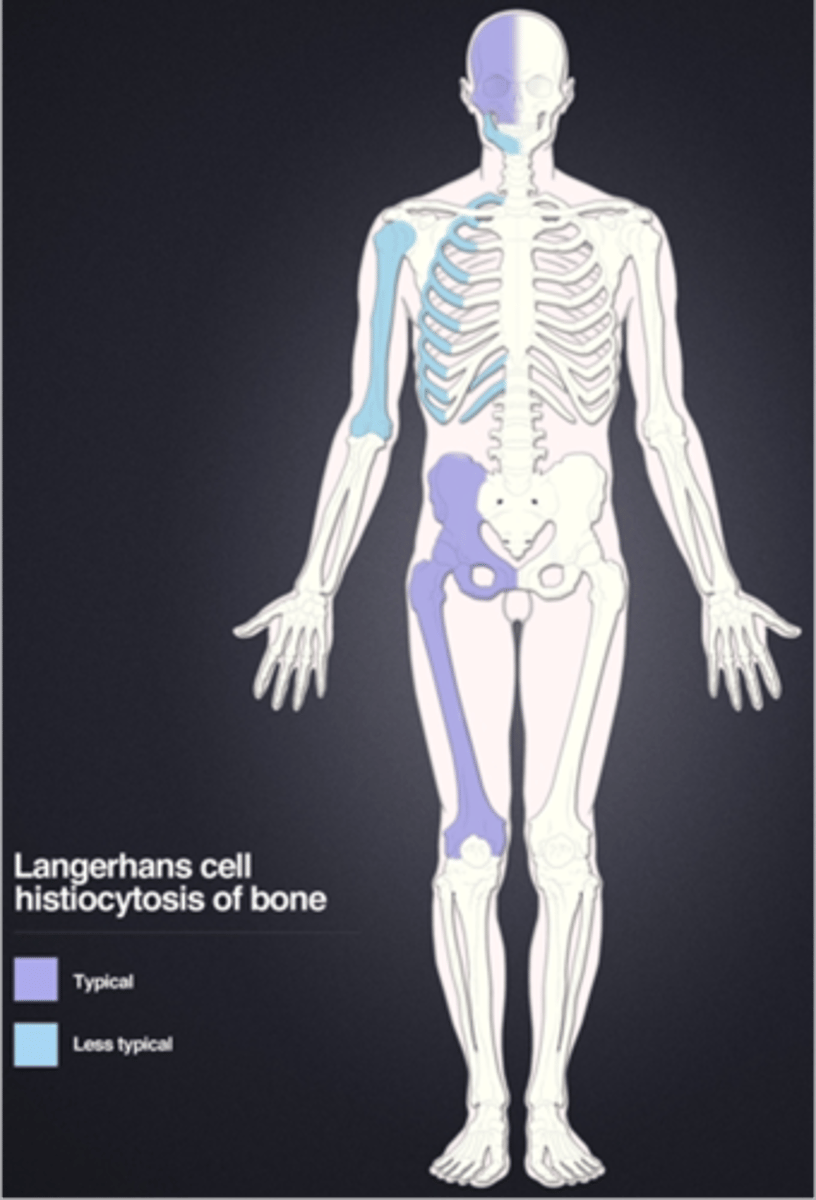

Langerhans Cell Histiocytosis

Eosinophilic granuloma is a type of _____

Eosinophilic granuloma

- <20 y.o. (peak 5-10 y.o.)

- Skull, mandible, pelvis, spine

- Monostotic > polyostotic

Beveled edge

ID radiographic feature of eosinophilic granuloma in the skull

Button sequestrum

ID radiographic feature of eosinophilic granuloma in the skull

Eosinophilic granuloma in the spine

ID benign tumor